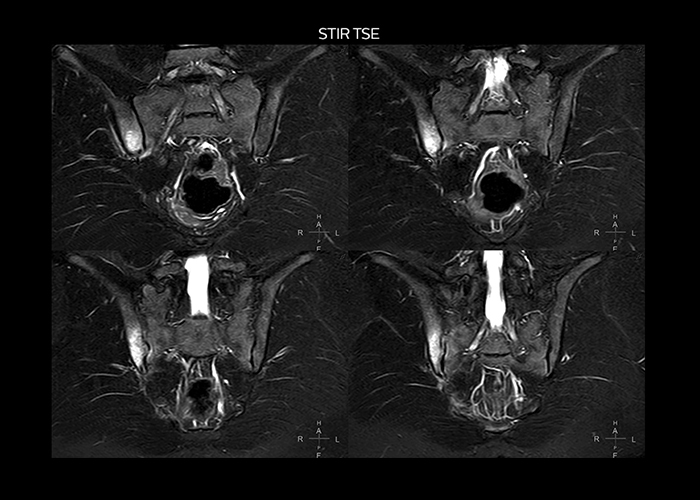

“To avoid coil changes we plan examinations of similar anatomies back to back, such as head and spine. Multiva helps us here a lot because coils don’t need to be changed frequently. Moreover, thanks to parallel imaging technology and 16-channel HeadSpineTorso and 8-channel MSK coils we are able to achieve excellent image quality. In this way Multiva helped us to increase both image quality and productivity.”

“Neurological cases, such as brain and spine imaging, represent the largest share in our MR scanning, followed by musculoskeletal cases. In general, we use simple and basic imaging protocols. But occasionally, we use advanced techniques for problematic cases if necessary.

“Most important, Multiva satisfies our clinical imaging needs very well,” says Mr. Tuna. “Many features of Multiva have become similar to the Ingenia system. Even in more complex imaging such as abdominal and cardiac, the image quality and performance of Multiva is better than we expected. General surgeons and physicians from our hospital’s internal medicine department prefer to refer to us because of this.”